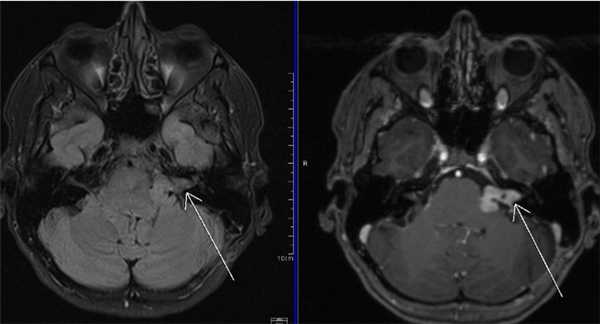

МРТ головного мозга. На мрт в аксиальной плоскости отмечается объемное образование внутреннего слухового прохода слева (стрелка), с четкими и неровными контурами, деформирующее окружающие структуры. После внутривенного введения парамагнитного контрастного вещества отмечается интенсивное и неоднородное его накопление образованием (изображение справа) — невринома.

Липома ММУ (указана стрелками) на снимке МРТ головного мозга в аксиальной проекции